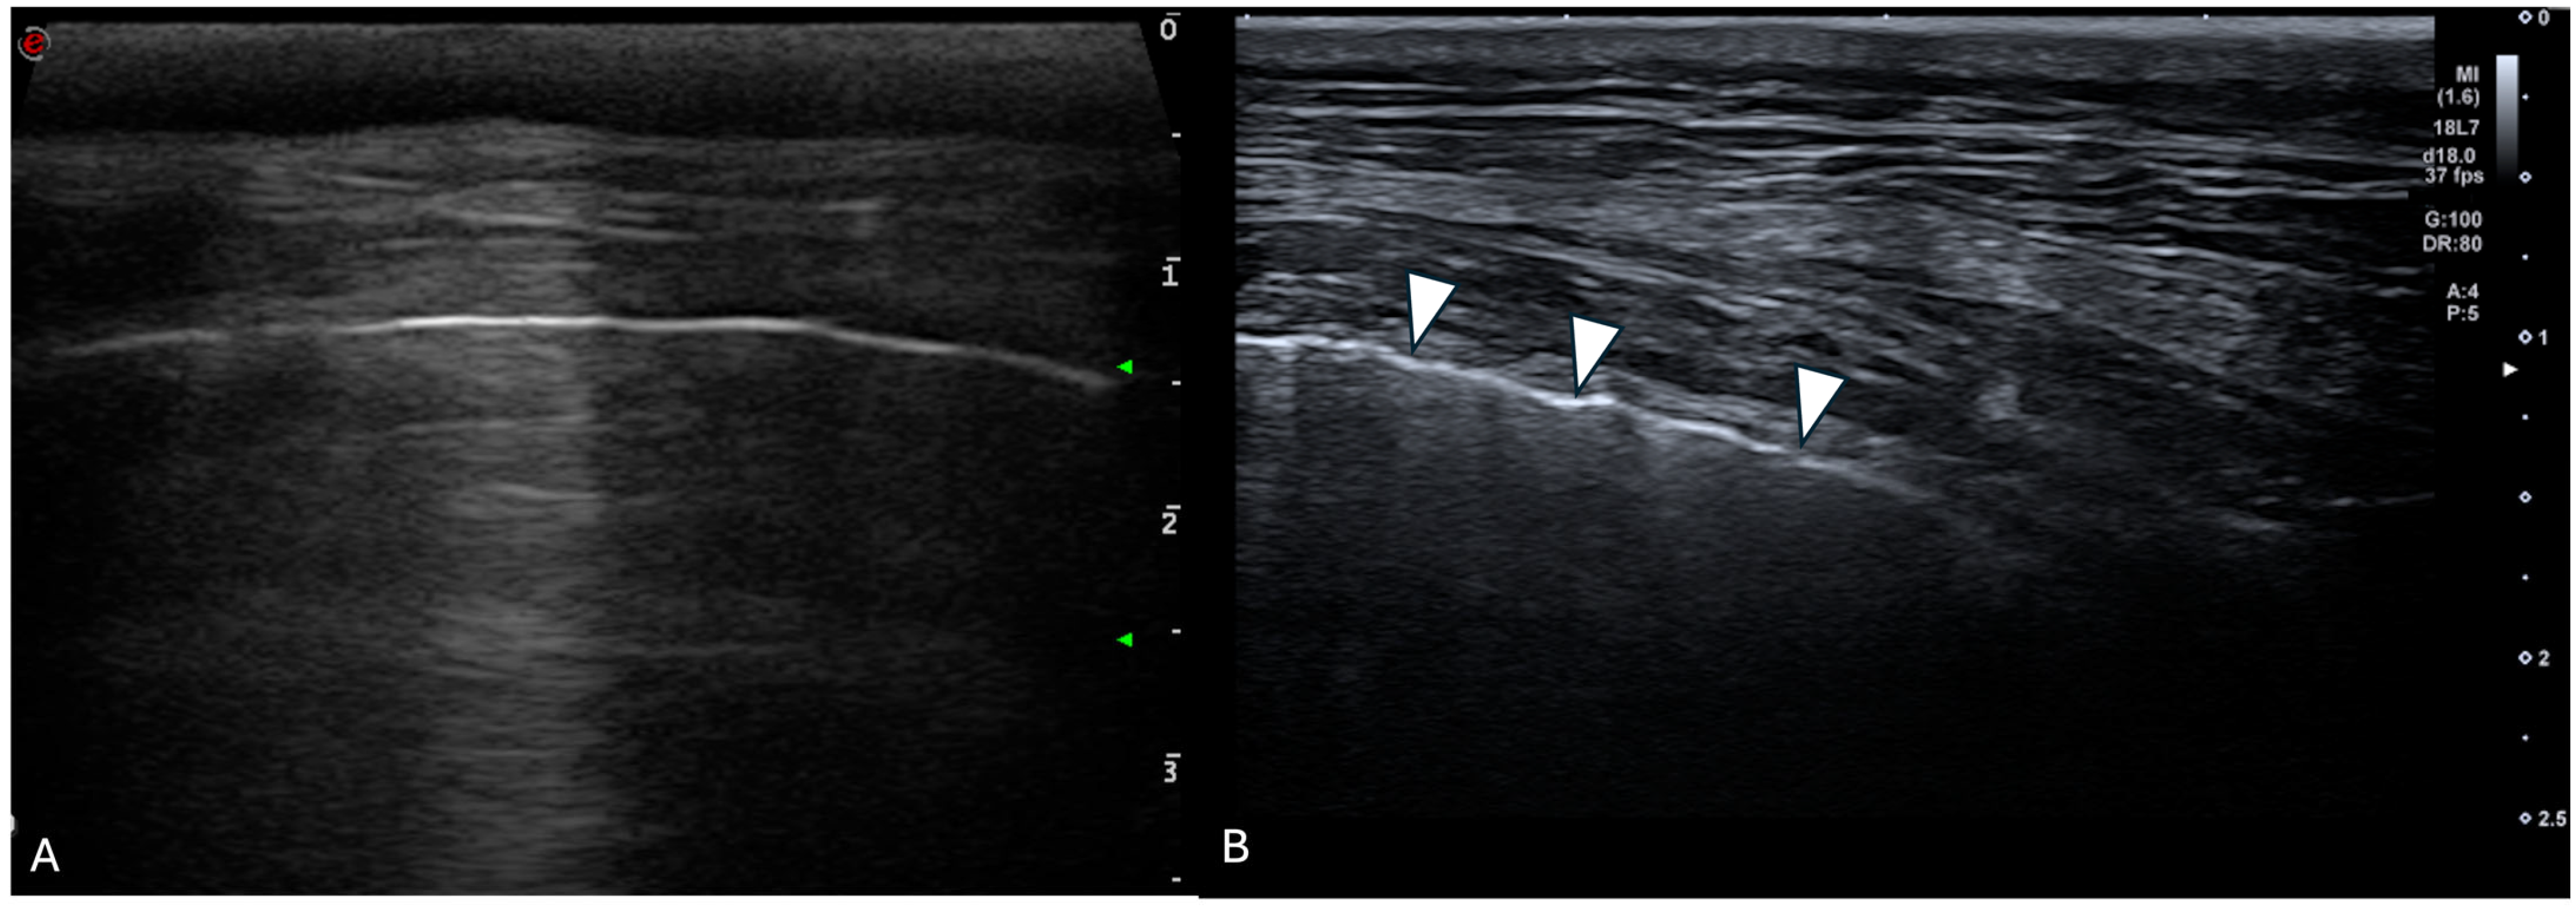

For each location, the presence and the number of ring-down artefacts (Figure 1) were counted. Depending on the number of artefacts, a score was obtained from 0 to 3 (Table 1). A similar method was applied for other lung lesions, such as peripheral hypoechoic pulmonary nodules or hypoechoic pulmonary areas (Table 1, Figure 2). The pleural surface was defined as smooth or irregular (Table 1, Figure 3)—scores of 0 or 1—and pleural sliding was assessed as present or absent (Table 1)—scores of 0 or 1. Pleural effusion was assessed as present or absent—scores 0 or 1 (Table 1). The scores were summed for each location and each side, and a total score out of 72 was attributed to each dog. Examinations were performed by the same operator (GB) on all dogs in a blinded fashion.

Figure 1. Ultrasonographic image of the thorax of a WHWT affected with CIPF showing ring-down artefacts (white arrows). The image was obtained in a transverse orientation (parallel to the ribs).